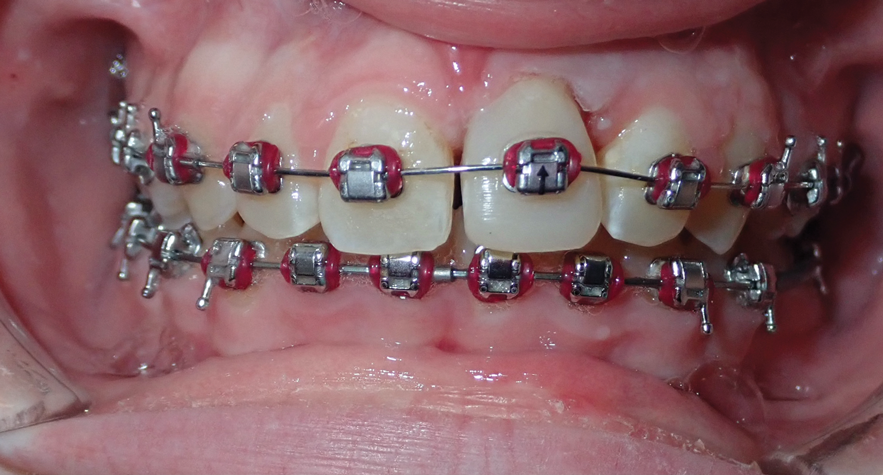

A third risk of using an implant to replace a missing lateral incisor is the continued vertical growth of the alveolar bone and eruption of the teeth adjacent to the implant.9,10 Traditionally, it has been taught that an implant can be safely placed when alveolar bone growth is confirmed complete with serial radiographs. However, numerous studies call that rule into question.11-16 Bernard et al evaluated vertical changes in teeth adjacent to implants in a young group of patients (15.5 to 21 years) and in a mature group (40 to 55 years), over a mean time of 4.2 years.17 In the young group, infraocclusion of the implant crowns ranged from 0.1 mm to 1.65 mm, while in the mature group the infraocclusion of the implant crowns ranged from 0.12 mm to 1.86 mm. An example of infraocclusion that occurred in a young implant patient over time is depicted in Figure 3 and Figure 4. Based on classic literature as cited here, it seems prudent to delay the placement of implants in high-risk areas, such as the maxillary lateral incisor region, for as long as possible or perhaps avoid it altogether.

Fig 3. Implants were placed in a 20-year-old female patient in the Nos. 7 and 11 sites with a pontic replacing No. 10.

Fig 4. A 15-year postoperative photograph of the patient in Fig 3 illustrates the significant infraocclusion of the implants compared to the natural teeth. Also, note the blue tissue discoloration over implants Nos. 7 and 11.